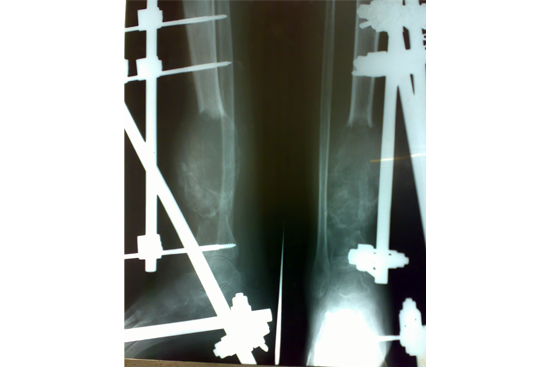

Tibialisation of Fibula

Method

We have done Huntington technique by stage ilizarov procedure. Here is the diagrammatic representation of our method.